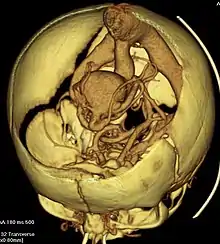

| Axial image from computerized tomography angiogram showing arteriovenous communication in vein of Galen malformation | |